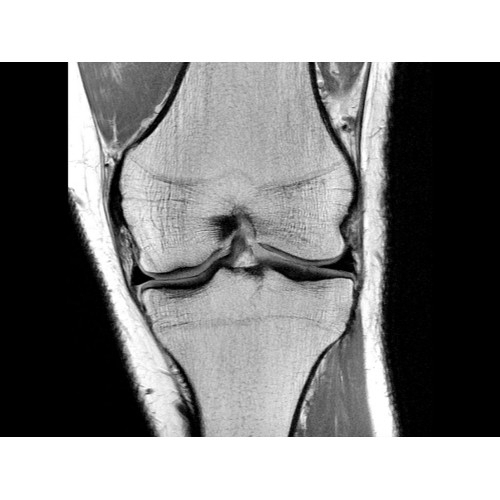

МР-томограф Optima MR450w позволяет получать изображения исключительно высокого качества, которые помогают установить диагноз. Чтобы удовлетворить ожидания клиентов в отношении высокого качества, в МР-томографе Optima MR450w были сохранены дополнительные возможности платформы Discoverу, привнесшие в его работу универсальность и мощь.

• Градиентная подсистема eXtreme — мощная градиентная подсистема для исследования тела характеризуется градиентом 34 мТл/м и скоростью нарастания градиента 150 Тл/м/с по каждой оси, что обусловливает быстроту, точность и высокую воспроизводимость сканирования.

• Цифровой РЧ-приемник OpTix — эксклюзивная оптическая РЧ-система увеличивает четкость сигнала и его интенсивность, формируя чистые и резкие изображения.